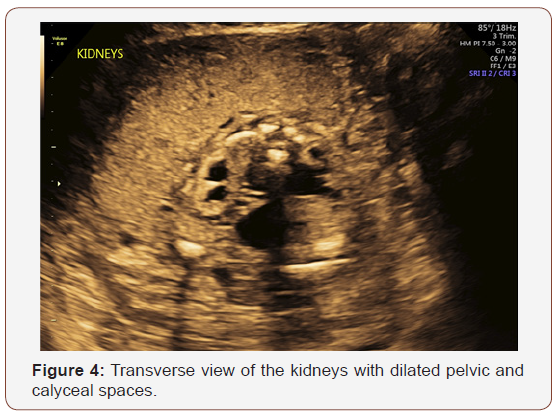

Fetal anatomy survey performed at 20 weeks gestation revealed multiple fetal anomalies, including bilateral cystic dilation of the pelvic and calyceal spaces, bilateral hydronephrosis, an enlarged urinary bladder, and oligohydramnios. Several sonographic images suggested a dilated posterior urethra, demonstrated by the pathognomonic “keyhole appearance”. PUV was suspected at this time and close follow-up was recommended. The patient was evaluated again at 22 weeks gestation, and a targeted fetal ultrasound revealed worsening oligohydramnios with persistent distention of the urinary system. These findings confirmed the suspicion of posterior urethral valve disorder.

The patient was counseled on the findings and expectations of this anomaly during the anatomy scan and genetic testing was offered. Amniocentesis showed elevated AFP (23.1 mcg/mL) and chromosomal analysis revealed a 46XY fetus. Additionally, the chromosomal micro assay exhibited a fetal chromosomal abnormality: arr [hg19] 16q24.2 (88, 059, 561-88, 647, 325) x 3. Approximately 588 kb interstitial gain of 16q24.2 was detected in this male fetus. This duplication included a segment of the BANP gene (OMIM: 611564), complete copies of the genes ZNF469 (612078), ZFPM1 (601950) and MIR5189, plus a segment of the ZC3H18 gene (not annotated in OMIM) (Figures 1-5).